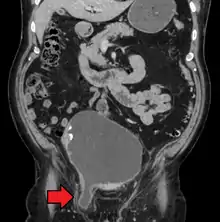

An inguinal hernia which contains part of the bladder. Bladder cancer also present.